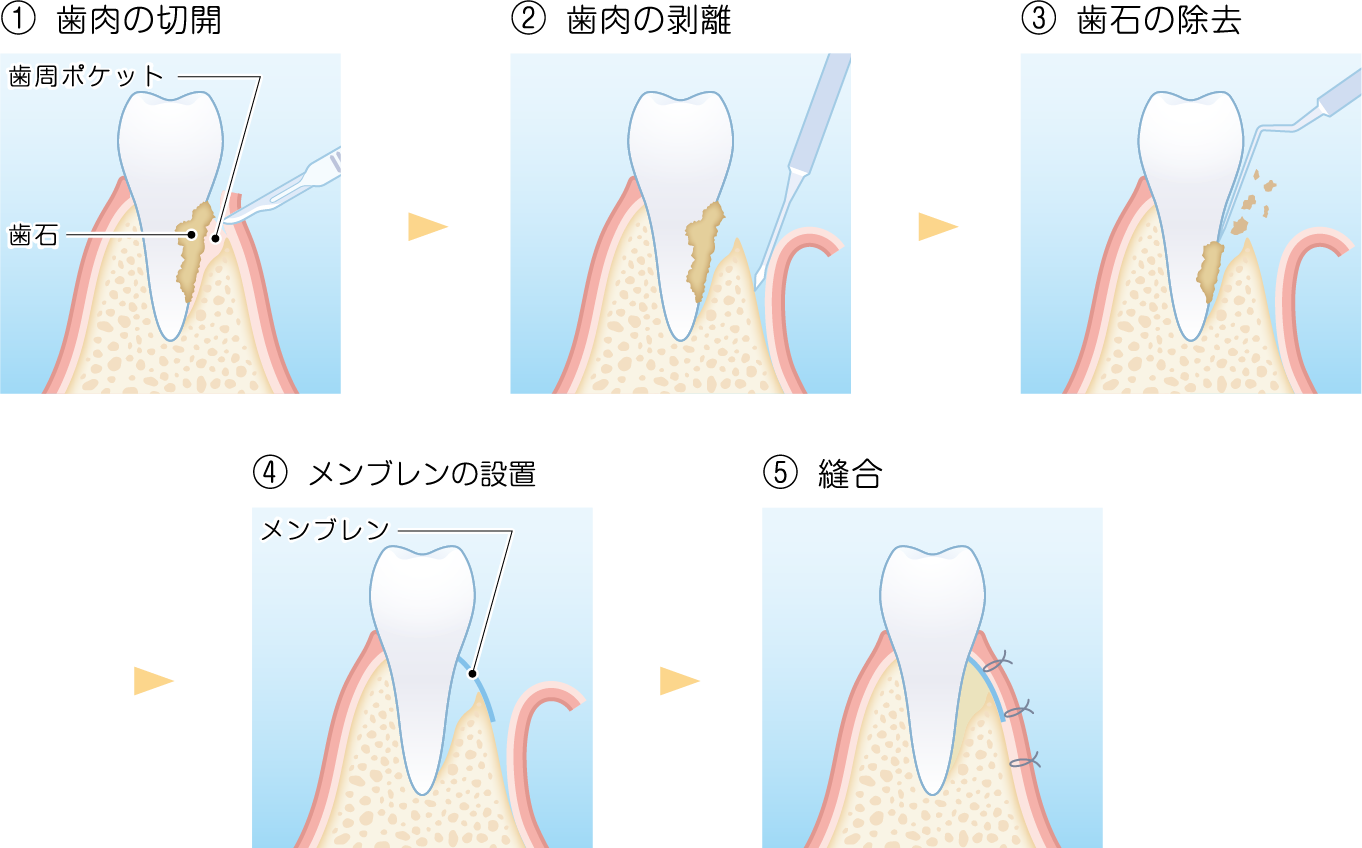

従来の歯周病治療とは異なり、組織が歯根面に到達することをメンブレン(人工膜)で防ぐことにより、歯根膜をもととした組織/細胞の新生を伴う結合組織性付着を形成できるようにする方法です。

歯周病によって歯を支える歯槽骨が溶けてしまっている場合などに、メンブレン(人工膜)を挿入しておくことで歯ぐきの侵入を防ぎつつ歯周組織の再生するスペースを確保できます。